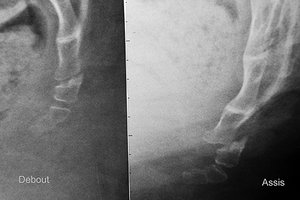

Dislocation of the coccyx (left: standing; right: seated).

There are two significant pathological findings you may miss without the sitting X-ray. One is dislocation: a coccyx that completely loses its normal relationship to the other coccygeal segments or the sacrum when sitting. In a dislocation, a segment of the coccyx has shifted or translated.

The second is hypermobility: a coccyx segment that has more than 25 degrees of motion (usually into flexion), comparing the standing film to the sitting film. Both of these findings represent excessive motion. The pictures below show these findings.

When you have either of these findings on the dynamic coccyx X-ray, you know there has been significant anatomical damage to the coccyx. In either of the above scenarios (dislocation or hypermobility), the ligaments are quite likely to be damaged and lax. I have talked a lot about functional hypermobility over the past few years. Here is a place where we can see and measure anatomical hypermobility. If the patient has excessive coccyx motion, it means something damaged those ligaments. This is a very small set of bones and ligaments which can be easily traumatized in a fall.